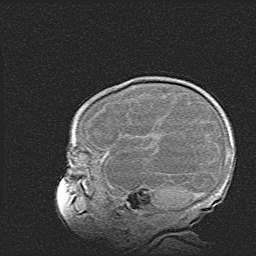

Церебральная ишемия II.

Возраст: 5 дней

Вес: 3400 г

Пол: женский

Окружность головы: 35 см

Срок гестации: 39 недель

Церебральная ишемия – это заболевание, характеризующееся недостаточностью (гипоксией) либо полным прекращением (аноксией) снабжения мозга кислородом по причине закупорки одного или нескольких сосудов. Это приводит к  что метаболическим расстройствам различной степени тяжести в тканях головного мозга, развитию коагуляционных некрозов и гибели нейронов.